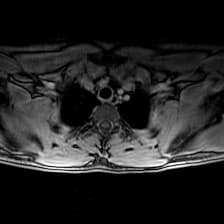

Subacute combined degeneration of the cord - enhancing